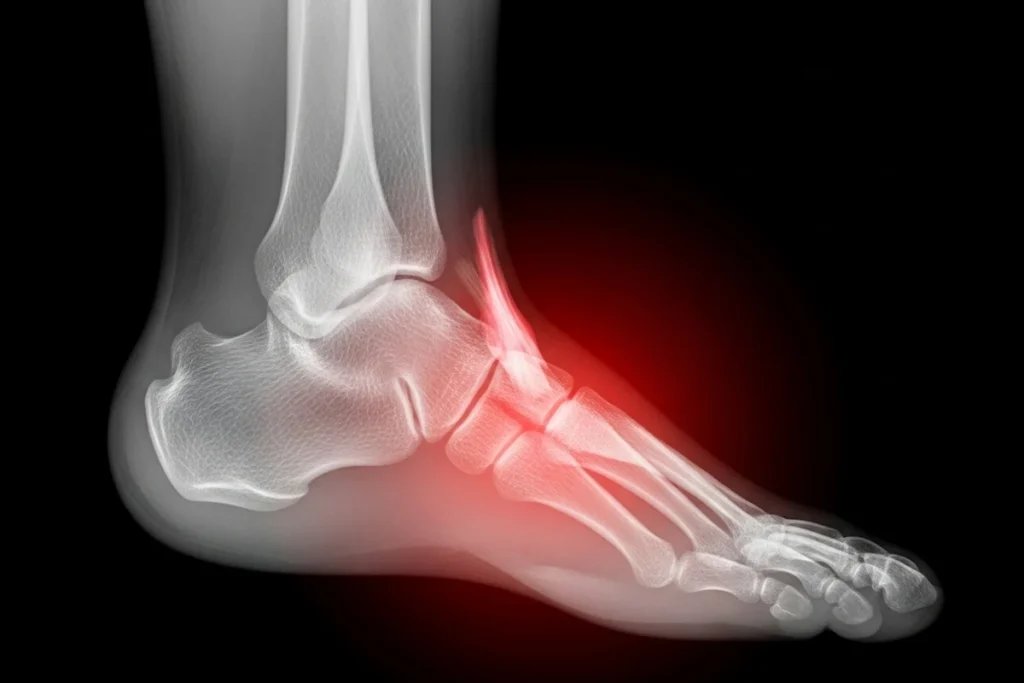

A twisted or rolled ankle happens when the ankle-supporting ligaments are stretched or torn, especially when you step on uneven surfaces or suddenly change direction. This usually happens when the foot turns in an awkward direction, and causes stress on the ligaments. You might sprain your ankle during activities like walking, running, or sports, and create the need for ankle sprain treatments in Chandler.

To determine the best ankle sprain treatment in Phoenix, our team will start by assessing your symptoms. We’ll ask about how the injury occurred and examine the ankle for swelling, bruising, and mobility. In some cases, we may recommend an X-ray or MRI to ensure there are no fractures and to assess the ligament damage in more detail.